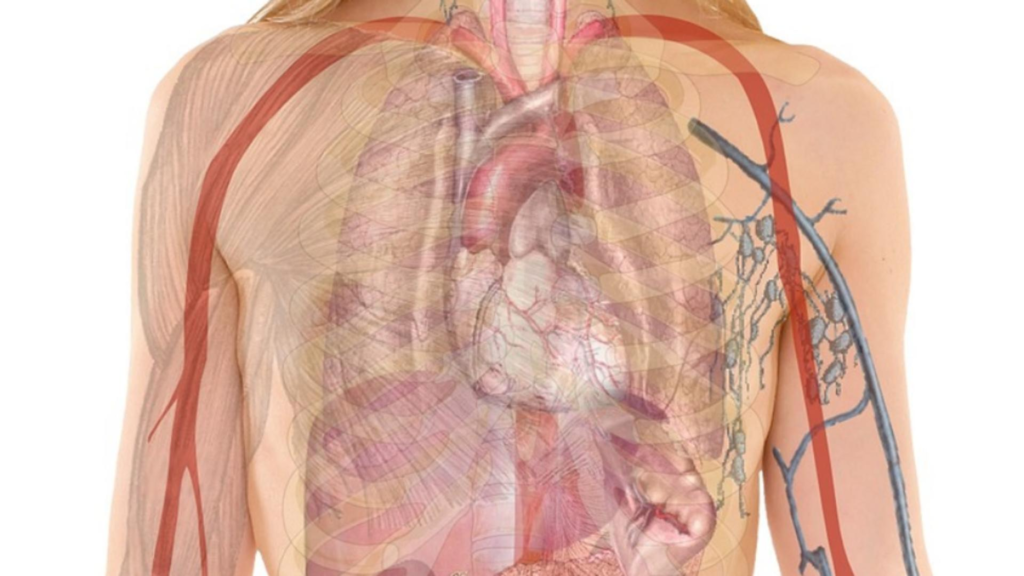

Roșia și inima: susținerea motorului corpului

Cu patru camere ce amintesc de structura inimii, roșia reprezintă un adevărat cardioprotector. Licopenul, pigmentul care oferă roșiei culoarea intensă, a fost asociat cu reducerea riscului de boli cardiovasculare. Un strop de ulei de măsline crește absorbția acestui nutrient de zece ori, transformând-o într-un aliat suprem al sănătății inimii. Nu e doar hrană, e medicament.

Grapefruitul și sânii: prevenție naturală

Structura unui grapefruit amintește de glandele mamare, iar substanțele sale active fac mai mult decât o asemănare vizuală. Limonoidul prezent contribuie la prevenirea cancerului de sân, promovând un flux sănătos al limfei. Este alimentul pe care femeile ar trebui să-l ia în serios.